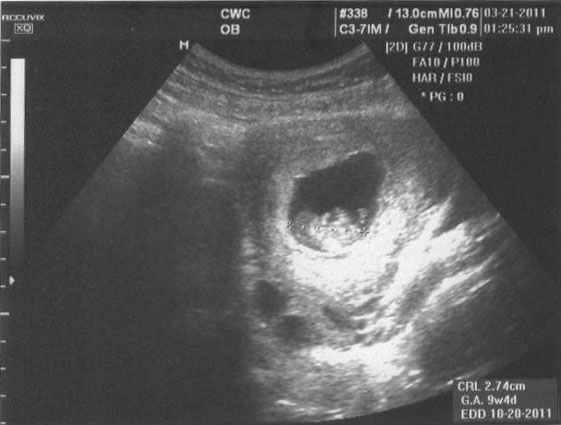

We are excited to announce that we are pregnant! It has already been hard on me but Fox is taking care of me the best he can. Here is the first ultrasound picture we have. This is from a few weeks ago actually. Next ultrasound is later this week.